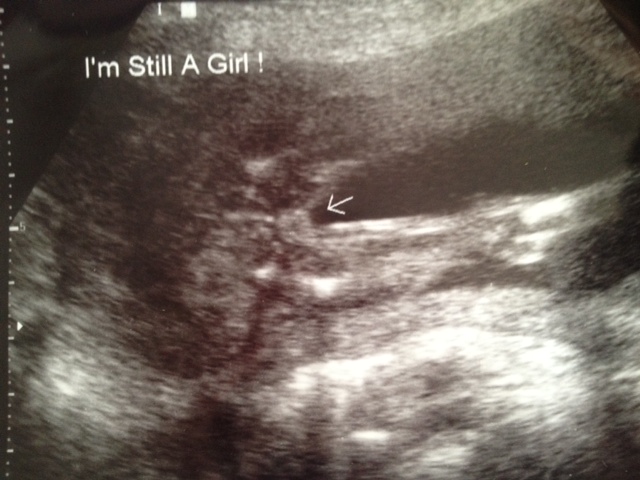

Hey girls! I just wanted to come and update because I know you guys like to get the nubs "confirmed" :) We went in at 16w for a gender scan...tech said she was 100% sure it was a girl at that time also. Here's the 16w0d shot:

Attachment 2757

I didn't want to come here and update off of that shot alone however because I didn't get my "little three white line" confirmation from that shot and I just wanted them to be SURE (she was...I was not convinced. lol) before I came here and posted. So I waited for the 20 week anatomy scan :) Again...she said 110% positive all girl! ;) So I'm updating :) I'll update our sway also in the appropriate swaying forum because we were swaying for pink :)